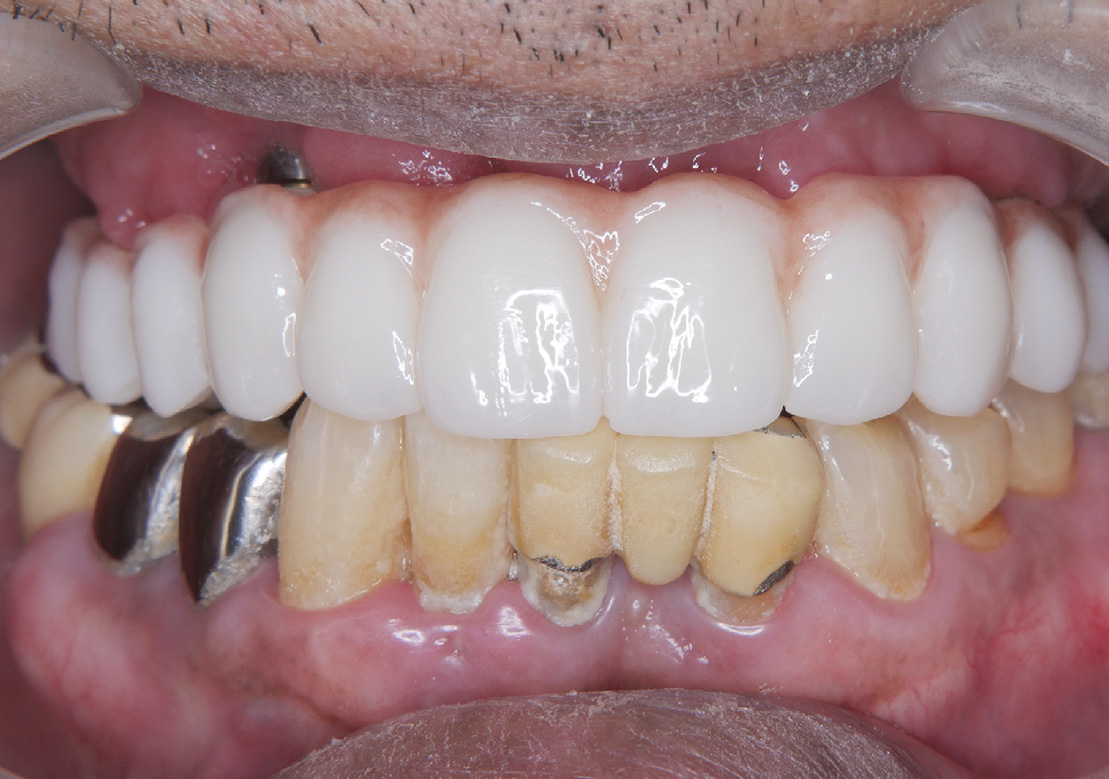

症例その3オールオン4

• Before

• After

咀嚼、審美障害。歯周病でグラグラな歯を全部抜歯してオールオン4で治療した症例。